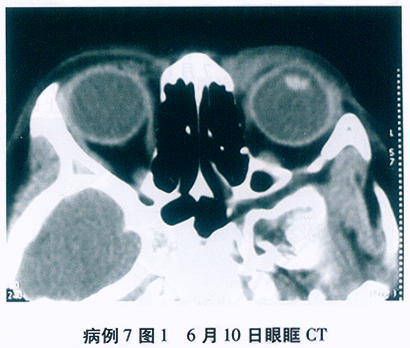

问题 1176

患者,男性, 28岁,主诉“双眼先后眼红、畏光、流泪、异物感9天, 左眼视力下降2天”。患者半月前曾至公共浴室洗浴,其后出现左眼红, 流泪,异物感等症状, 无明显分泌物,2天后右眼亦出现同样症状, 去医院就诊为“急性结膜炎”,予以局部抗病毒、抗生素滴眼液治疗, 但病情进一步发展,而且左眼出现视力下降, 遂至我院就诊。